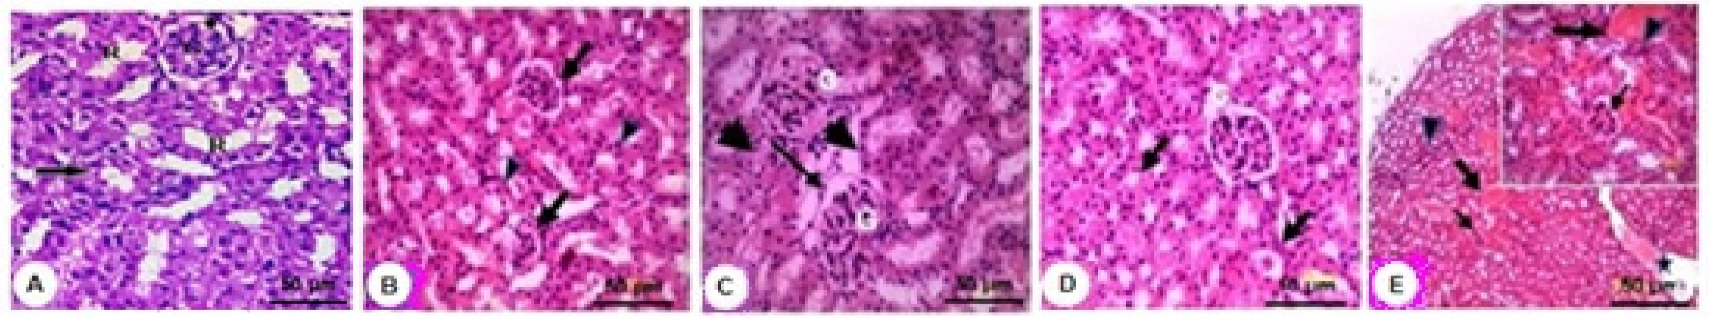

2.5. MLE Ameliorated Cd-Induced Liver and Kidney Tissue Damage